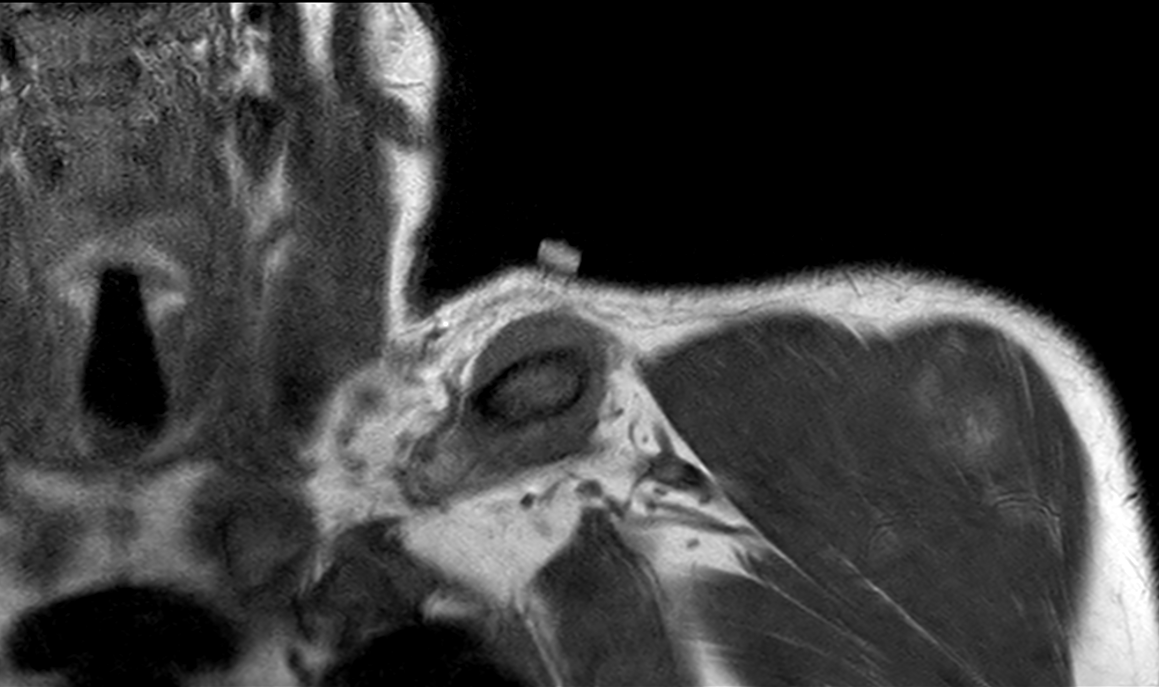

Consent ✅ Right hip pain & stiffness Both hip joints show OA changes - but R more advanced than L Why?

🕵️♂️ Dr. Murphey’s X-Files has arrived at Skeletal Radiology! 📂 Case #001 is now live. 👉 What’s the most likely diagnosis? 💡 Share your thoughts and come back to check the answer! Because, in the end, the truth is in the images. #SkeletalRadiology